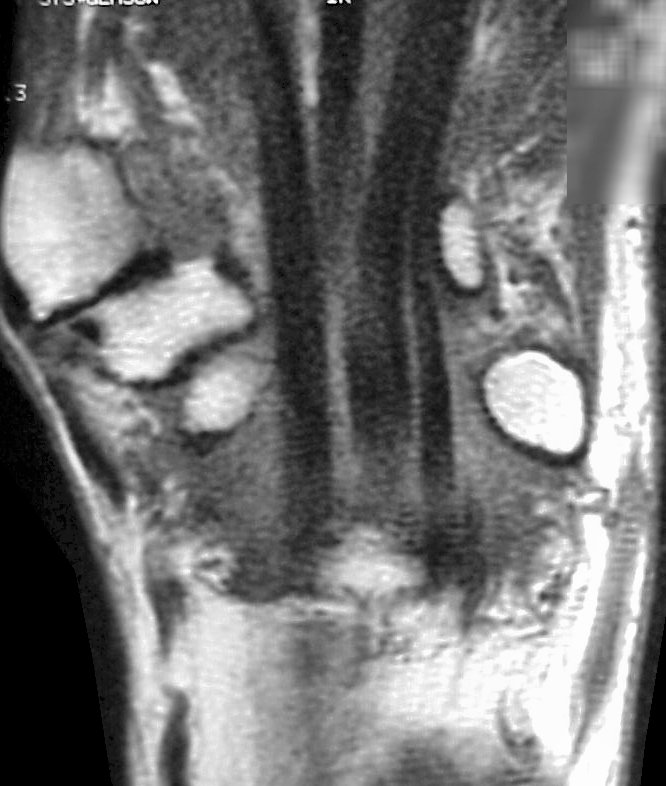

Sections through the carpal tunnel -  looking for a hook of hamate fracture or tendon discontinuity - were read as normal, although there may be a subtle signal irregularity through the hook of the hamate:

Click for larger image